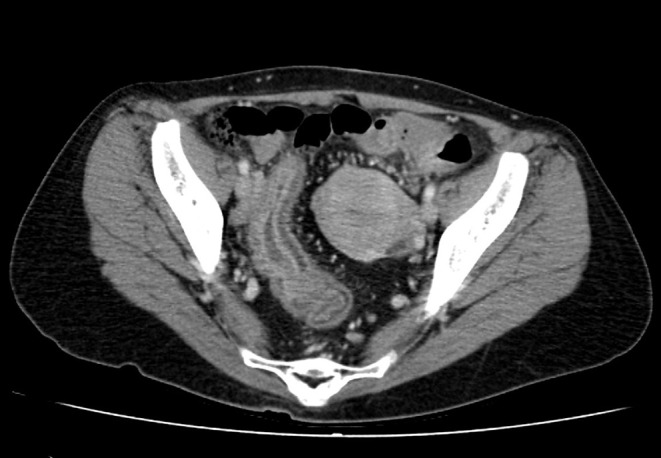

患者是一名 50 岁的日本女性,26 岁时被诊断出患有全结肠炎型溃疡性结肠炎(UC)。她接受了美沙拉嗪和硫唑嘌呤治疗,疾病活动得到了很好的控制。50 岁时,患者出现发热、腹痛、腹泻、血便和肛门疼痛,因此被诊断为 UC 复发。虽然进行了类固醇治疗,症状有所改善,但还是出现了粪便样阴道分泌物,并确诊为直肠阴道瘘(RVF)。患者接受了结肠造口术,并开始使用英夫利西单抗作为 UC 的维持治疗。所有症状均有所改善,在开始使用英夫利昔单抗 6 个月后,确认直肠阴道瘘闭合。迄今为止,她的 UC 一直没有复发。目前只有少数 UC 并发 RVF 的报道,而且这种情况通常很难治疗。据我们所知,此前还没有其他病例在接受结肠造口术和英夫利昔单抗治疗后瘘管闭合的病例;因此,我们对本例病例的报告在文献中具有重要价值。

The patient was a 50-year-old Japanese woman who was diagnosed with total-colitis-type ulcerative colitis (UC) at the age of 26 years. She was treated with mesalazine and azathioprine, and her disease activity was well controlled. At the age of 50 years, the patient was experiencing fever, abdominal pain, diarrhea, bloody stool, and anal pain, which led to a diagnosis of a relapse of UC. Although steroid therapy was administered and tended to improve her symptoms, fecaloid vaginal discharge occurred, and rectovaginal fistula (RVF) was confirmed. Colostomy was performed, and infliximab was initiated as maintenance therapy for UC. All symptoms improved, and RVF closure was confirmed 6 months after the initiation of infliximab. To date, she has been free from relapse of UC. There have been only a few reports of UC complicated by RVF, and this condition is often difficult to treat. To the best of our knowledge, no other case of UC complicated by RVF in which the fistula was closed after treatment with colostomy and infliximab has been previously reported; thus, our report of the present case is valuable to the literature.